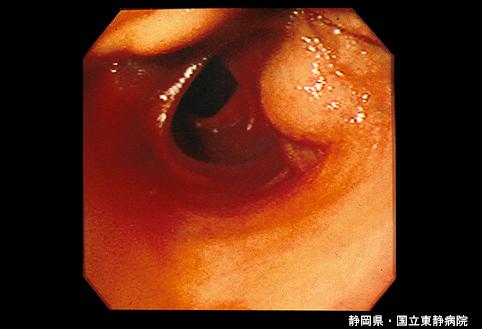

症例提示(所在地,施設名等): 静岡県・ 静岡医療センター (Dr. 尾関ら)

疾患(病理主体)の分類良性非上皮性腫瘍/血管腫

部位(臓器別)小腸/回腸

検査方法内視鏡

病変の最大径(ミリ)40以上